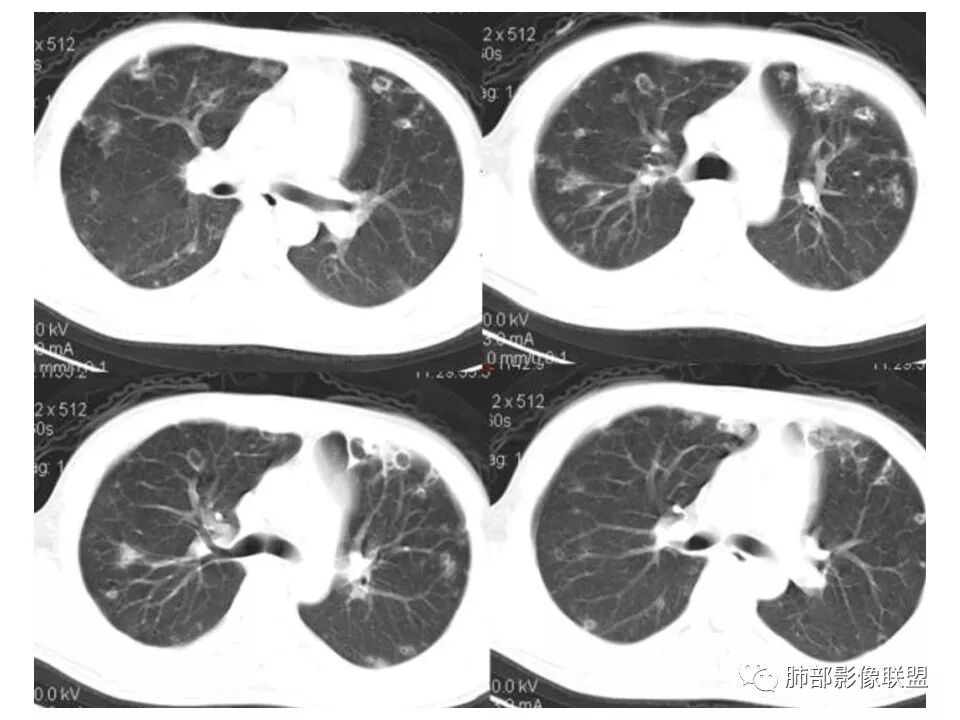

南边:青年男性,急性起病,多发结节或囊腔——胸膜下分布结节,与支气管关系不密切,支气管壁不增厚,首选血道来源,不是气道来源

南边:

血道来源的:

1、感染性:金葡菌?克雷白杆菌?曲霉菌?

2、血管炎性:血管炎?

3、肿瘤:血管肉瘤?转移瘤?

结果

(血源性)金葡菌肺炎(血培养金黄色葡萄菌)

金黄色葡萄球菌:革兰阳性菌,涂片表现为成对的短链状四联球菌或簇状。金葡菌肺炎:是由金黄色葡萄球菌引起的急性化脓性肺部感染,常发生于免疫功能受损的病人。主要分为原发性(吸入性)金葡菌肺炎和继发性(血源性)金葡菌肺炎。血源性金葡菌肺炎:常继发于金葡菌败血症及脓毒血症,由细菌栓子经血液循环至肺而引起。多表现为肺外周和基底部分布为主的多发点片状影或类圆形结节影。菌栓引起多发性肺小动脉栓塞,导致双肺多发性化脓性炎症,进而组织坏死形成多发性肺脓肿,并可累及胸膜产生脓胸或脓气胸。诊断要点:    1.金黄色葡萄球菌引起3%的社区获得性肺炎及15%的  医院获得性肺炎    2.金黄色葡萄球菌肺炎的主要危险因素是静脉输液和ICU患者。    3.常见的影像学表现:    1)单侧(60%)或双侧(40%)斑片状实变影(支气管肺炎)    2)空洞性结节(直径4~10mm)

3)CT可见小叶中心结节、树芽征及楔形变(脓毒性栓塞)

4)肺气囊形成

5 ) 脓肿形成

6 ) 胸腔积液

少见的影像学特征:弥漫性肺实变(表示支气管肺炎融合)